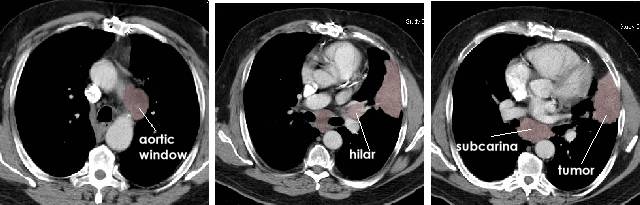

CT scans below show a patient with a large left lung cancer with spread to the lymph nodes, higher up the aortic_window nodes (N2 level 5) lower down the hilar nodes (N1 level 11) and then further down the subcarinal nodes (N2 level 7)

lung_typical_nodes_bmc.jpg (28853 bytes)